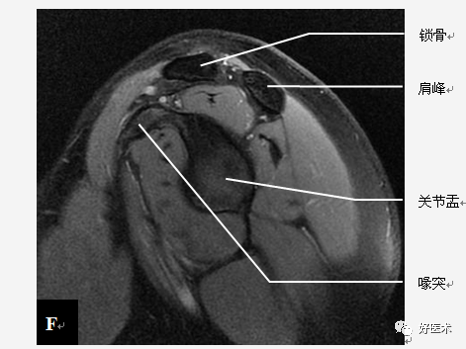

肩关节是一个复杂的关节,它由多个关节、多块肌肉、多条韧带之间相互作用,形成身体中一个独特的区域。熟悉相关解剖是快速诊断、成功手术必备要素,尤其是对于刚开始做肩关节手术的医师更为重要。今天采用高清图谱讲解肩关节影像解剖,值得学习借鉴!

肩关节骨骼构成

三块骨:肩胛骨、锁骨、肱骨

两个关节:

肩锁关节

盂肱关节